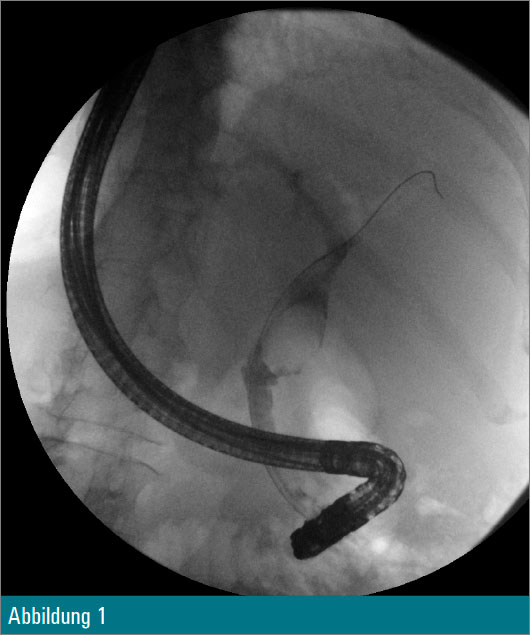

Eine 55-jährige Patientin wurde wegen eines Tonnenkonkrements im Ductus choledochus zur ERCP vorstellig (Abbildung 1). Nach Papillotomie erfolgte zusätzlich eine Ballondilatation der Papille auf 12 mm. Anschließend wurde mit dem Cholangioskop in den Ductus choledochus eingegangen (Abbildung 2) und eine elektrohydraulische Zertrümmerung des Konkrements unternommen (Abbildung 3).